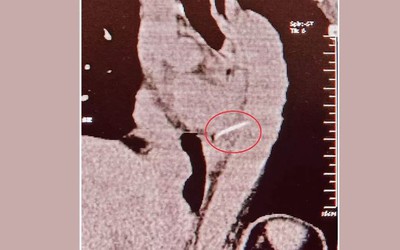

Người phụ nữ 54 tuổi đã vô tình nuốt phải một chiếc xương cá dài 4cm. Sau đó, bà bị đau ngực dữ dội và được đưa đến bệnh viện.